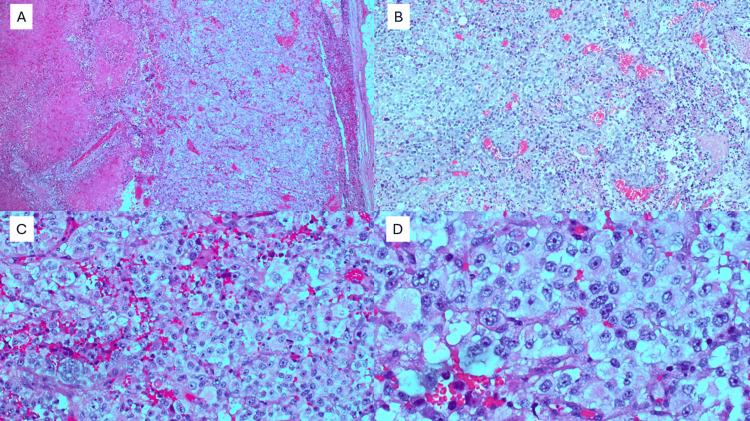

Thoracic SMARCA4-deficient undifferentiated tumor (TSDUT) is a rare and quite new classification of primary pulmonary malignancy. It is classified as a non-small cell lung cancer, typically associated with smoking, and is highly aggressive. Its clinical features, immunohistochemistry, and pathology are quite unique. In this case report, we describe the clinical course of TSDUT pancoast tumor in a 40-year-old male, without a substantial smoking history, but a significant history of occupational welding.

胸段SMARCA4缺陷型未分化肿瘤(TSDUT)是原发性肺恶性肿瘤中一种罕见且较新的分类。它被归类为非小细胞肺癌,通常与吸烟有关,且具有高度侵袭性。其临床特征、免疫组化和病理学都相当独特。在本病例报告中,我们描述了一名40岁男性TSDUT潘科斯特瘤的临床病程,该患者无大量吸烟史,但有显著的职业焊接史。